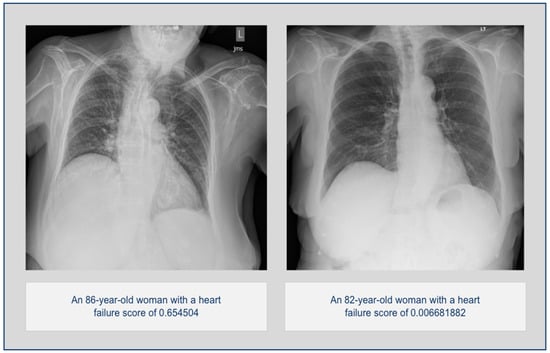

Early Detection of Heart Failure with Autonomous AI-Based Model Using Chest Radiographs: A Multicenter Study